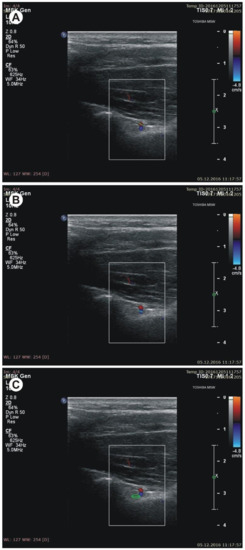

- the thickness of the soft tissue over the suprascapular artery: the minimal distance between the suprascapular artery and the skin (Figure 4A)

- the thickness of the soft tissue over the suprascapular vein: the minimal distance between the suprascapular vein and the skin (Figure 4B)

- the thickness of the soft tissue over the suprascapular nerve: the minimal distance between the suprascapular nerve and the skin (Figure 4C).